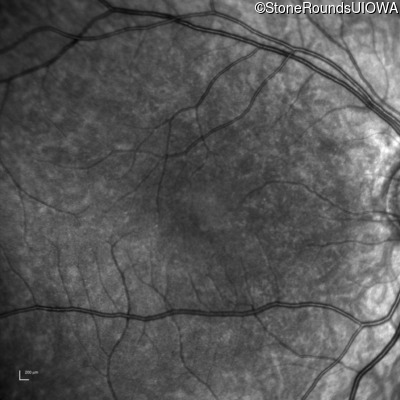

Infrared Fundus Photograph - Left - 10/200 sc

Exemplar